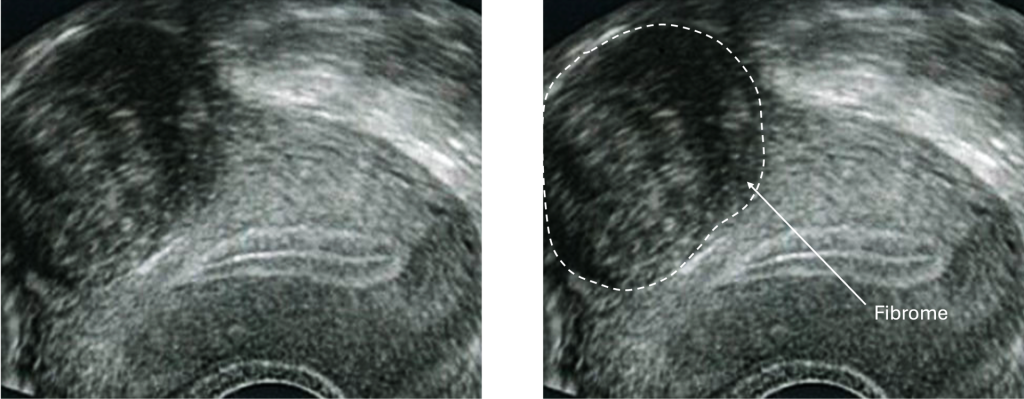

L’échographie pelvienne

Elle est indolore, rapide et permet de visualiser la taille et l’emplacement des fibromes (s’ils ne sont pas trop nombreux ou trop volumineux).

Elle peut se faire par voie abdominale ou endovaginale (avec une sonde introduite dans le vagin pour une meilleure visibilité).

Chaque femme peut avoir un seul fibrome ou plusieurs, de types différents. Le diagnostic se fait généralement par échographie ou IRM, selon la situation.